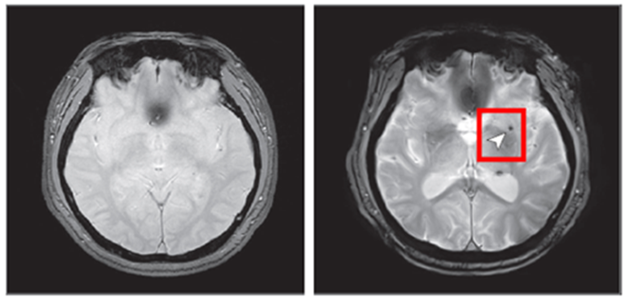

< 8년 후 뇌 미세출혈이 발생한 뇌영상 이미지 >

노화 기반 참여 8년 후 추적조사 참여